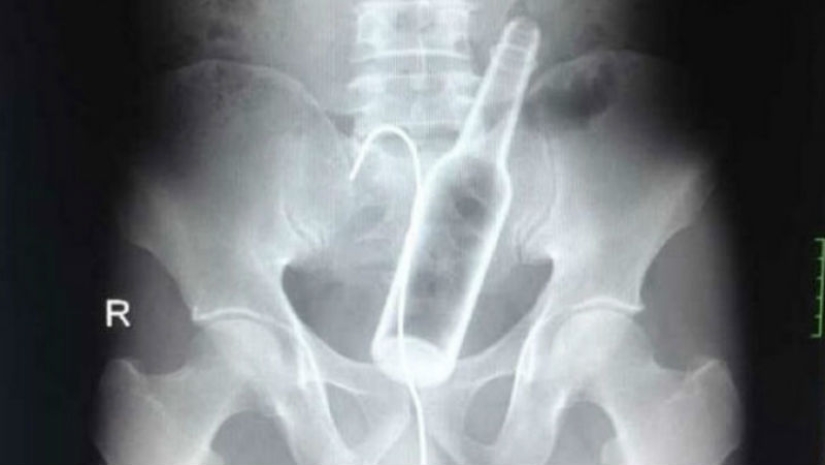

A man came to one of the Chinese hospitals with complaints of abdominal pain. Los médicos tomaron una radiografía y encontraron una botella de vidrio en el estómago.